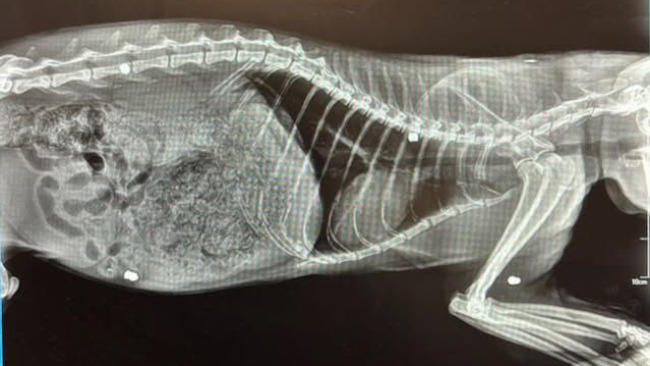

Odrobaczono go i wykastrowano, przeleczono świerzbowca i naprawiono ząbki. Zdjęcia RTG ukazały 4 śruty tkwiące w jego ciele, do tego stwierdzono niedowład ogona (prawdopodobnie po spotkaniu z samochodem) i częściową utratę wzroku. Na koniec... test na białaczkę wyszedł dodatni. Pełny pakiet nieszczęść...